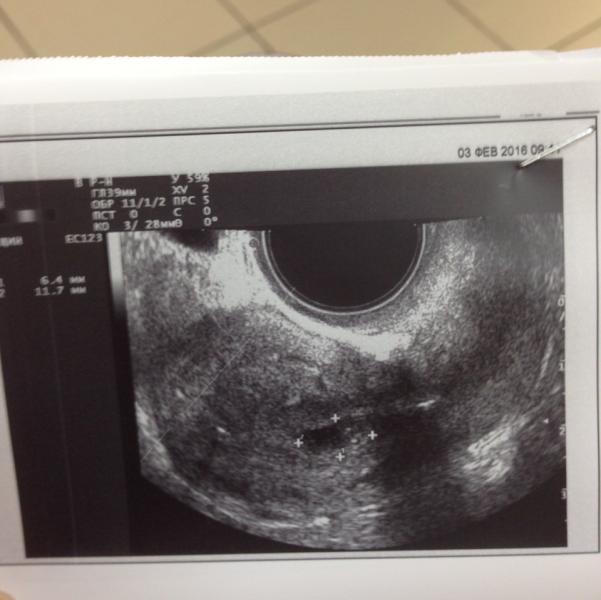

Вот фото моего плодного яйца от 3 февраля. 3-4 недели беременности по мнению врача УЗИ. Вот думаю не может это быть например миома? Или невозможно спутать?

Миома выглядит по-другому. Если есть полость, в котором плодное яйцо, то определенно беременность. И рост ХГЧ доказывает наличие беременности.

Могу прислать фото своей миомы недалёко от плодного яйца. Совсем не то 🤔 тут Пя с четким овалом, а миома выглядит как облако или тучка с размытыми краями